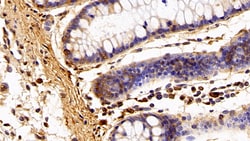

Ionized calcium-binding adapter molecule 1 (IBA1), also known by its gene name AIF1, is a protein expressed predominantly by microglia in the brain and spinal cord. This protein belongs to the EF-hand calcium-binding protein family and plays a crucial role in microglial activation and migration in response to brain injury or neuroinflammation. IBA1's function is integral to microglial motility and phagocytic activity, facilitating the cellular response to pathogenic stimuli and promoting tissue homeostasis and repair in the central nervous system. IBA1 serves as a reliable marker for activated microglia in various neurological disorders, including Alzheimer's disease, Parkinson's disease, and multiple sclerosis, where increased expression correlates with disease progression and severity. The protein's structural features enable it to bind calcium ions, inducing conformational changes that activate signaling pathways essential for microglial function. Its expression is highly regulated by inflammatory cytokines, underpinning its role in neuroimmune responses. Due to its specific expression in microglia during pathological conditions, IBA1 is widely used in research as a marker to study microglial status and activity, and it remains a focal point for understanding microglial involvement in neurodegenerative diseases.Specifications

| Immunohistochemistry (Paraffin), Western Blot | |